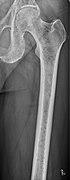

Medical imaging

The diagnostic examination of a person with suspected multiple myeloma typically includes a skeletal survey. This is a series of X-rays of the skull, axial skeleton, and proximal long bones. Myeloma activity sometimes appears as "lytic lesions" (with local disappearance of normal bone due to resorption). And on the skull X-ray as "punched-out lesions" (pepper-pot skull). Lesions may also be sclerotic, which is seen as radiodense.[52] Overall, the radiodensity of myeloma is between −30 and 120 Hounsfield units (HU).[53] Magnetic resonance imaging is more sensitive than simple X-rays in the detection of lytic lesions, and may supersede a skeletal survey, especially when vertebral disease is suspected. Occasionally, a CT scan is performed to measure the size of soft-tissue plasmacytomas. Bone scans are typically not of any additional value in the workup of people with myeloma (no new bone formation; lytic lesions not well visualized on bone scan).